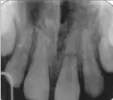

На данном рентгеновском снимке прослеживается поперечный перелом корня зуба. В данной ситуации тактика подбирается индивидуально, в зависимости от клинической симптоматики. Пульпу (сосудисто-нервный пучок) у данного зуба удалили, так как она была травмирована. Потемнение зуба после эндодонтического лечения может быть по многим причинам, начиная от физиологических процессов (так как нерв и сосуды были удалены, произошло нарушение трофики зуба) и заканчивая материалами, которые использовались во время лечения. Например, материал используемый в поликлиниках - резорцин-формалин, придает зубу от розовых до серо-коричневых оттенков. Следственно и дальнейшая тактика будет зависеть от причин.